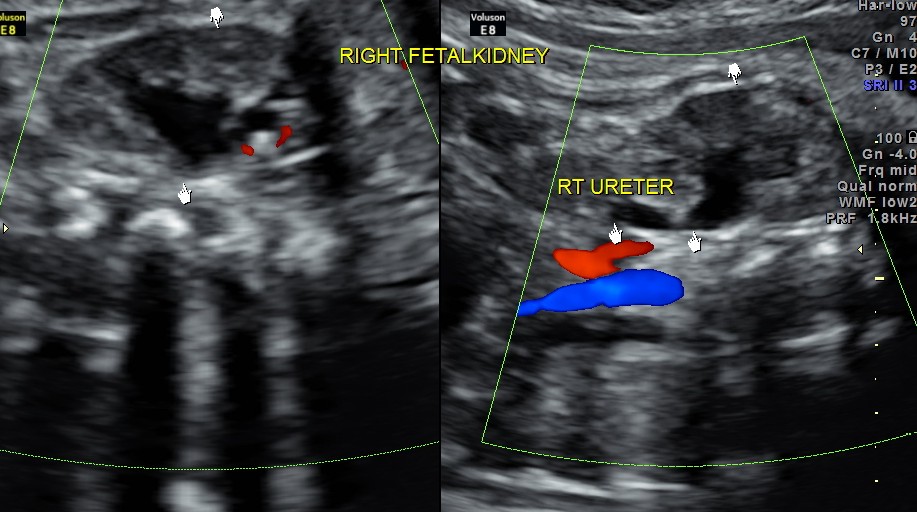

Rt proximal ureter is mildly dilated